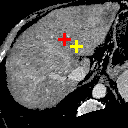

Refer to caption

(a)

(b)

(c) 12.49

(d) 0.9420

(e) 12.44

(f) 0.8593

(g) 13.28

(h) 0.8612

(i) 19.20

(j) 0.7311

Figure 6: Example comparison among VTN ADDD + inv (c/d), Elastix (e/f), ANTs (g/h) and VoxelMorph-2 (i/j). (a) sections of the fixed image (a CT liver scan); (b) sections of the moving image (another CT liver scan); (c/e/g/i) sections of the warped images and landmark distances; (d/f/h/j) sections of the warped segmentations (white for the fixed and semi-transparent red for the warped) and segmentation IoUs. Crosses indicate the projection of landmarks (L2, L3 and L4 from top to bottom), yellow (lighter) for one in the fixed image, red (darker) for the corresponding one in the moving/warped images. Best viewed in color.